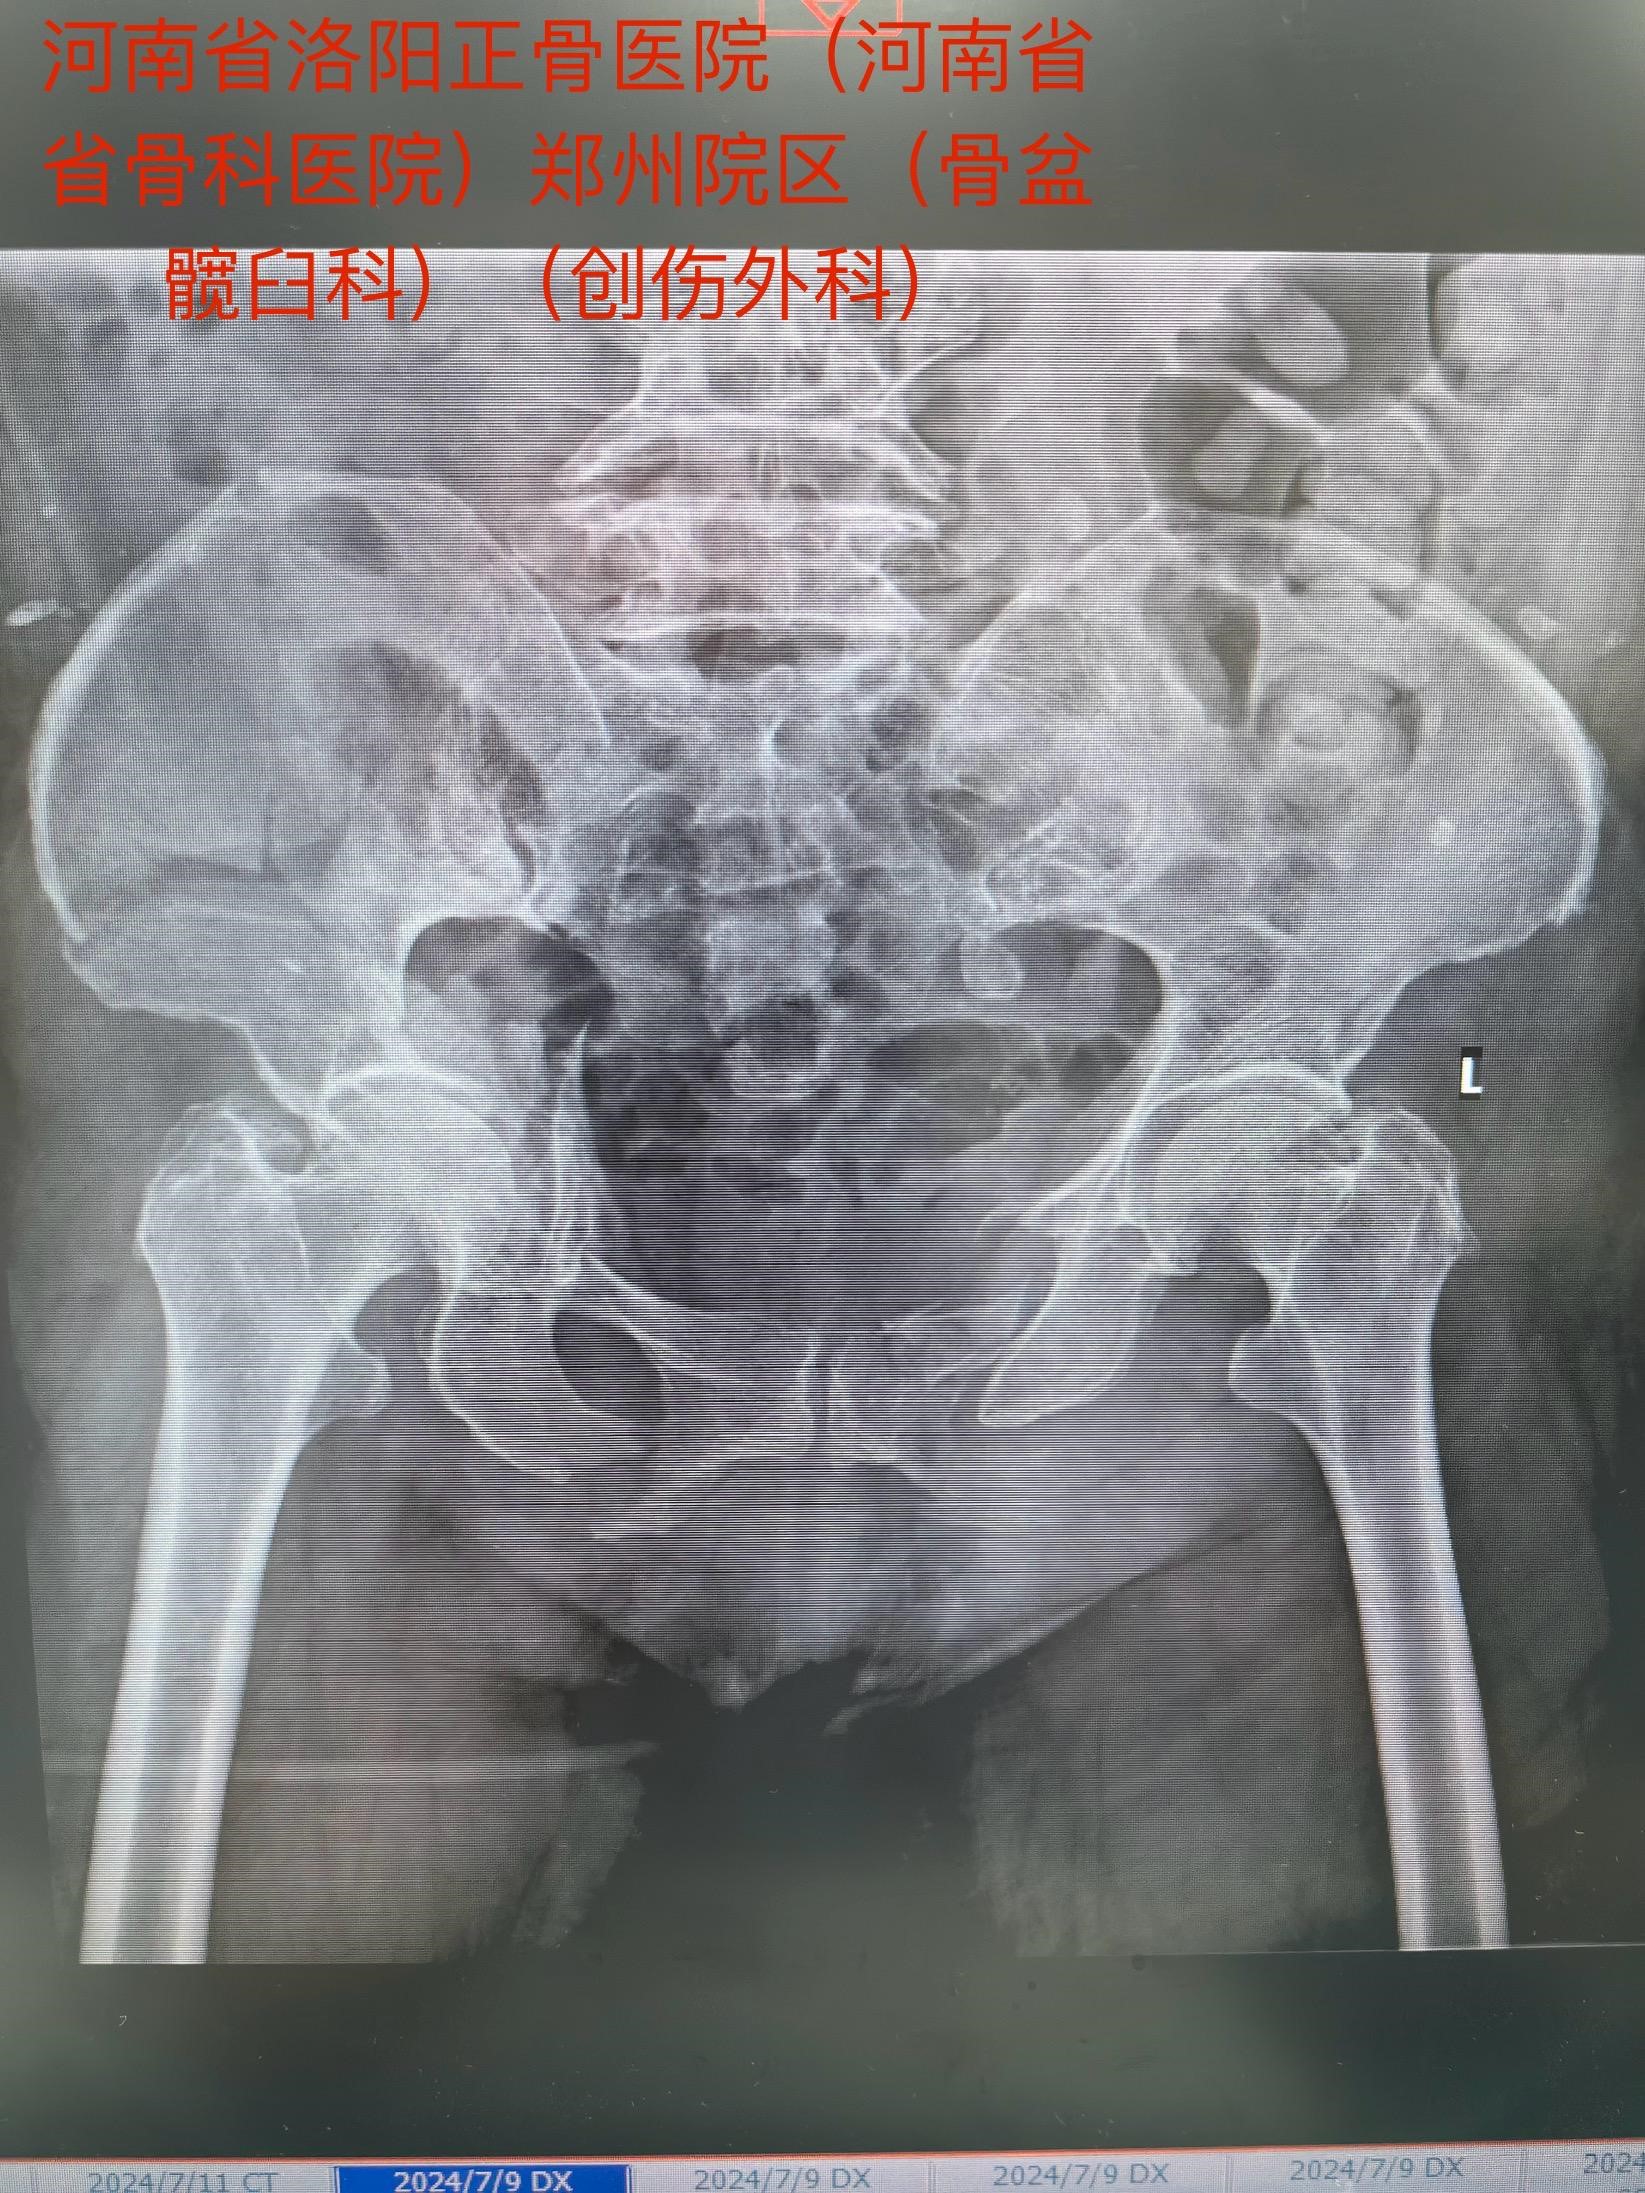

老人今年73岁,遭遇车祸后全身多处伤,在当地医院ICU治疗,生命体征平稳后,转入我院郑州院区。影像检查诊断:骨盆合并髋臼骨折,右侧髋臼双柱骨折……

马献忠主任积极倡导加速康复外科理念,对于老年骨盆髋臼骨折患者,他主张积极治疗。面对老人的复杂病情,马献忠主任积极组织多学科会诊,充分讨论,详细制定术前规划,为老人量身定制治疗方案。马献忠主任分两期进行手术:1期,右侧骨盆髋臼行单一髂腹股沟入路进行骨折复位及前后柱的固定。2期,进行左侧的微创骶髂螺钉固定骨盆后环。